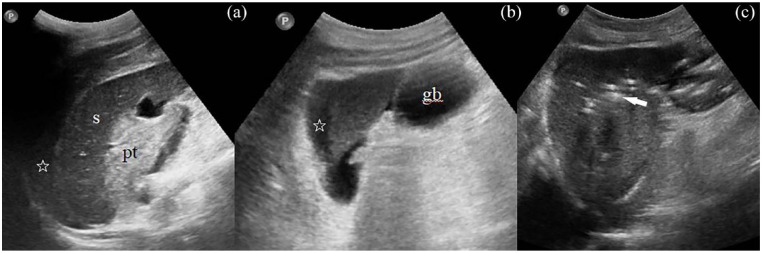

Splenic injury is an extremely rare complication of endoscopic retrograde cholangiopancreatography (ERCP). There are only 34 cases reported in the literature up to now. Based on a case of a 72-year-old man, who after ERCP due to choledocholithiasis developed a large perisplenic and subcapsular hematoma, we carried out an extensive review of all cases of ERCP-induced splenic injury found in the literature. We searched PubMed/Medline and Google Scholar till 15 April 2023, for published case reports and series using the following terms: splenic injury after ERCP, ERCP-induced splenic injury, and post-ERCP splenic trauma. The case reports included were in English, Spanish, and German literature. We attempt to discuss the possible clinical image, the available diagnostic methods, the potential treatment alternatives, and predisposing factors related to this entity. Furthermore, a theory of a possible mechanism of this injury is discussed and supported schematically. The ERCP-induced splenic injury is rare and a high index of suspicion is needed for diagnosis. Therefore, we present two diagnostic algorithms, which according to our opinion may assist the evaluation of this complication and lead to early accurate diagnosis and appropriate management. Collectively, our findings support that although ERCP-induced splenic injury is an unexpected/unusual complication of ERCP, following the proper steps can be timely diagnosed and treated.